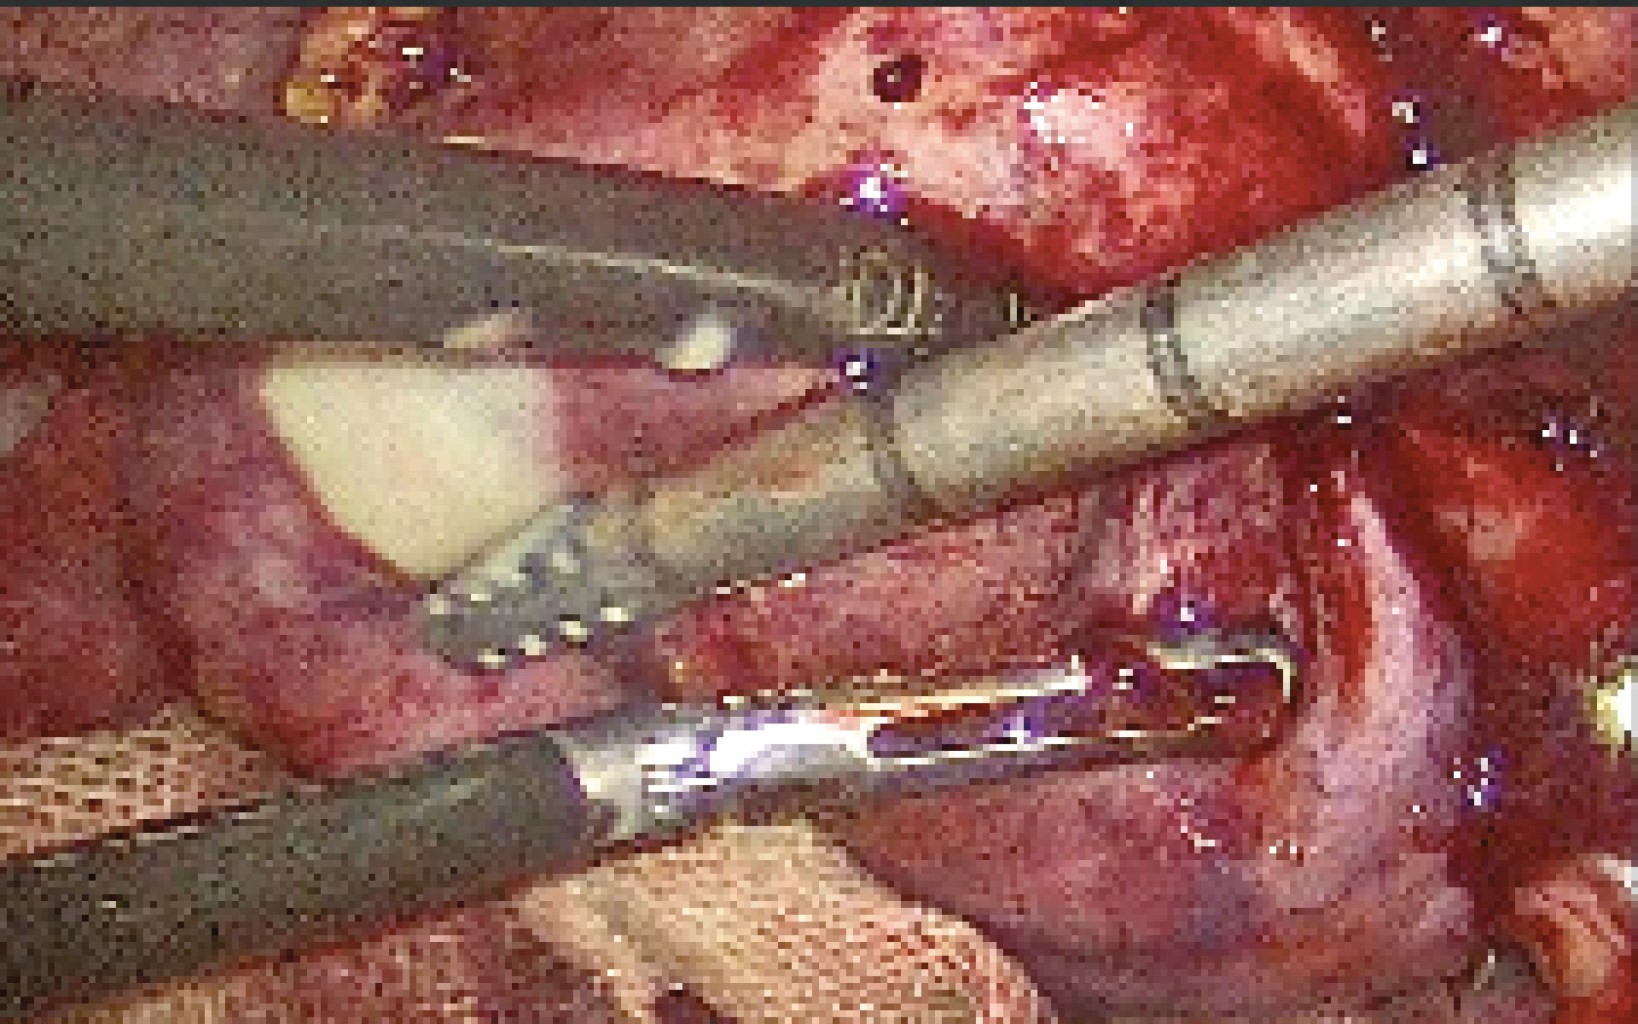

Antibiotic therapy based on carbapenems and imidazole was started with subsequent surgical management. Cholecystectomy plus abscess drainage and placement of drains by laparoscopy were performed. Four trocars of 12 mm were placed in the umbilical and subxiphoid region; in the hypochondrium and right flank, a 5 mm trocar was placed. We found a gallbladder covered entirely by omentum corresponding to Parkland 5 (Figure 4) with edematous walls and a hepatic abscess in segments IV and V adhered to the abdominal wall. Approximately 200 cm3 of purulent material (pyococcus and abscess) were drained (Figure 5), which were sent to culture, where growing of Streptococcus anginosus and Enterobacter cloacae was reported. The surgical piece was removed with an extractor bag, and finally, 19 Fr Blake-type closed drains were placed into the Winslow's hiatus and the abscess cavity, the patient was discharged home on the fourth postoperative day. The antimicrobial scheme was adjusted at discharge with ampicillin/sulbactam and metronidazole to complete 14 days of antibiotic therapy. In the follow-up consultation, on the seventh postoperative day, the patient was pain-free at the surgical site, afebrile, with good tolerance to oral administration and regular bowel movements. It was decided to remove both drains.

Figure 4